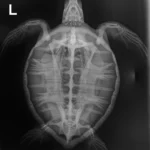

5.5 lbs./ 2.5 kg Atlantic Green Turtle non FP

Notches on rear flippers, abrasions on right front flipper, minor abrasions on plastron, abrasion under barnacle on head